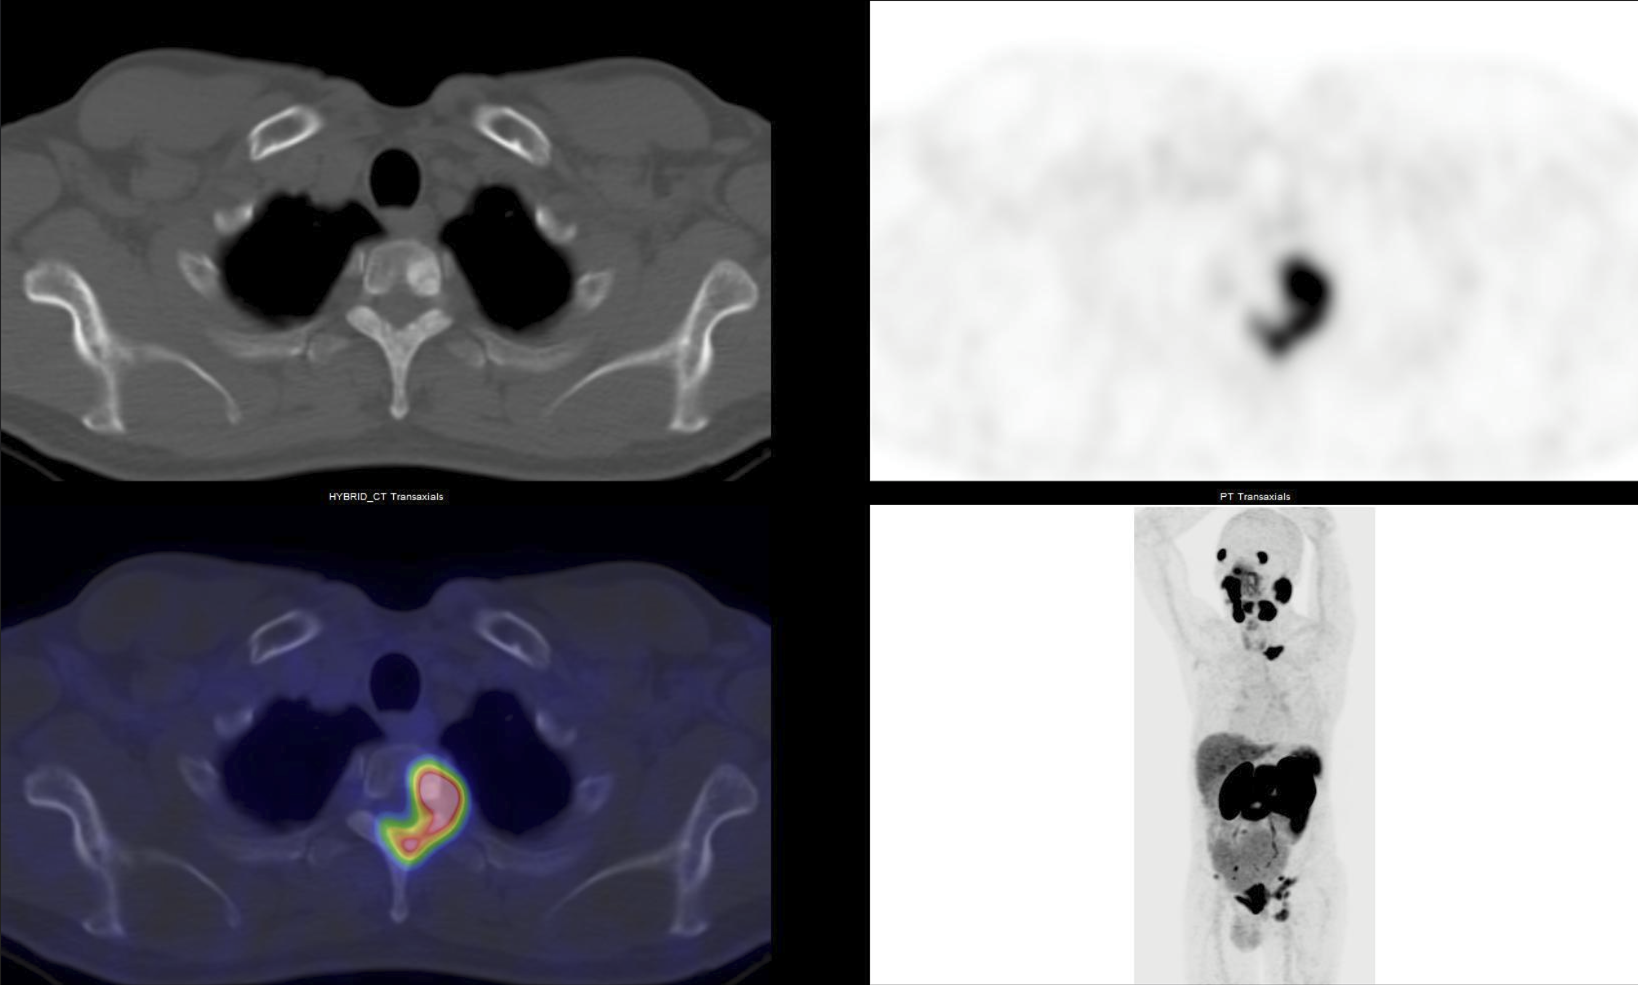

Hình ảnh 68Ga PSMA PET/CT ở bệnh nhân ung thư tuyến tiền liệt cho thấy tình trạng di căn xương. Ảnh: BVCC

Ở một số loại ung thư đặc thù, vai trò của y học hạt nhân càng được khẳng định rõ rệt, trong ung thư tuyến tiền liệt, PET/CT với 68Ga-PSMA là công cụ có độ nhạy cao trong phát hiện tái phát rất sớm, ngay cả khi nồng độ PSA chỉ tăng nhẹ.

Với các u thần kinh nội tiết, PET/CT sử dụng 68Ga-DOTATATE không chỉ giúp phát hiện tái phát mà còn định hướng điều trị bằng liệu pháp PRRT - một bước tiến quan trọng của y học hạt nhân hiện đại.